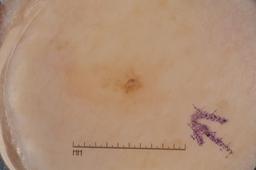

MSK-4

- Name: MSK-4

Description:

Images found based on a search for patients with a personal history, clinical diagnosis, or differential diagnosis of melanoma. All diagnoses confirmed by histopathology.